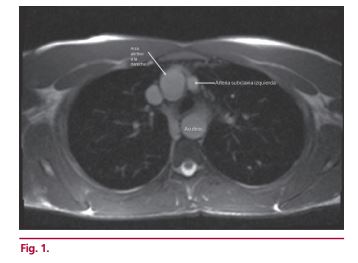

Arco aórtico derecho con subclavia izquierda aberrante que simula un doble arco aórtico

IMÁGENES EN CARDIOLOGÍA